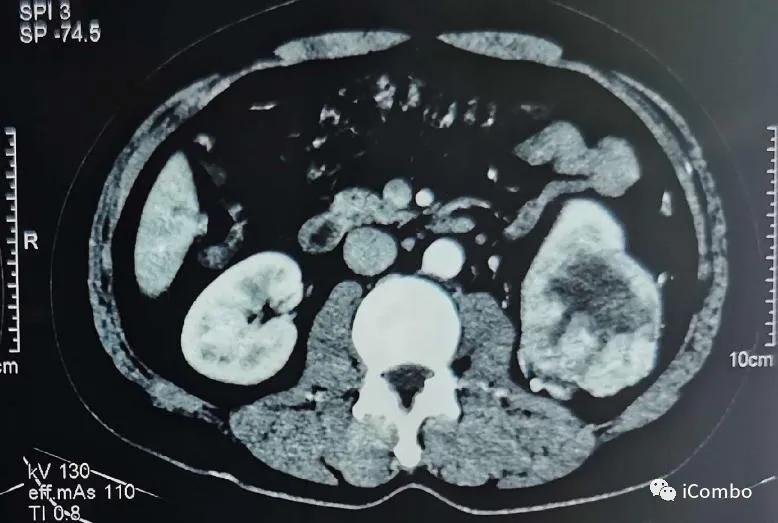

现病史:2012年行左肾癌根治术(肿瘤最大径7厘米),2018-9左髂部疼痛不适,考虑转移瘤,行索坦治疗。2019-06发现左胫骨肿块。2019-7-18 CT示肿瘤较前进展(107*84mm)。

CT:

2018.9左髂骨疼痛,穿刺确诊左髂骨转移

2019.6 肿瘤进展,骨痛加剧